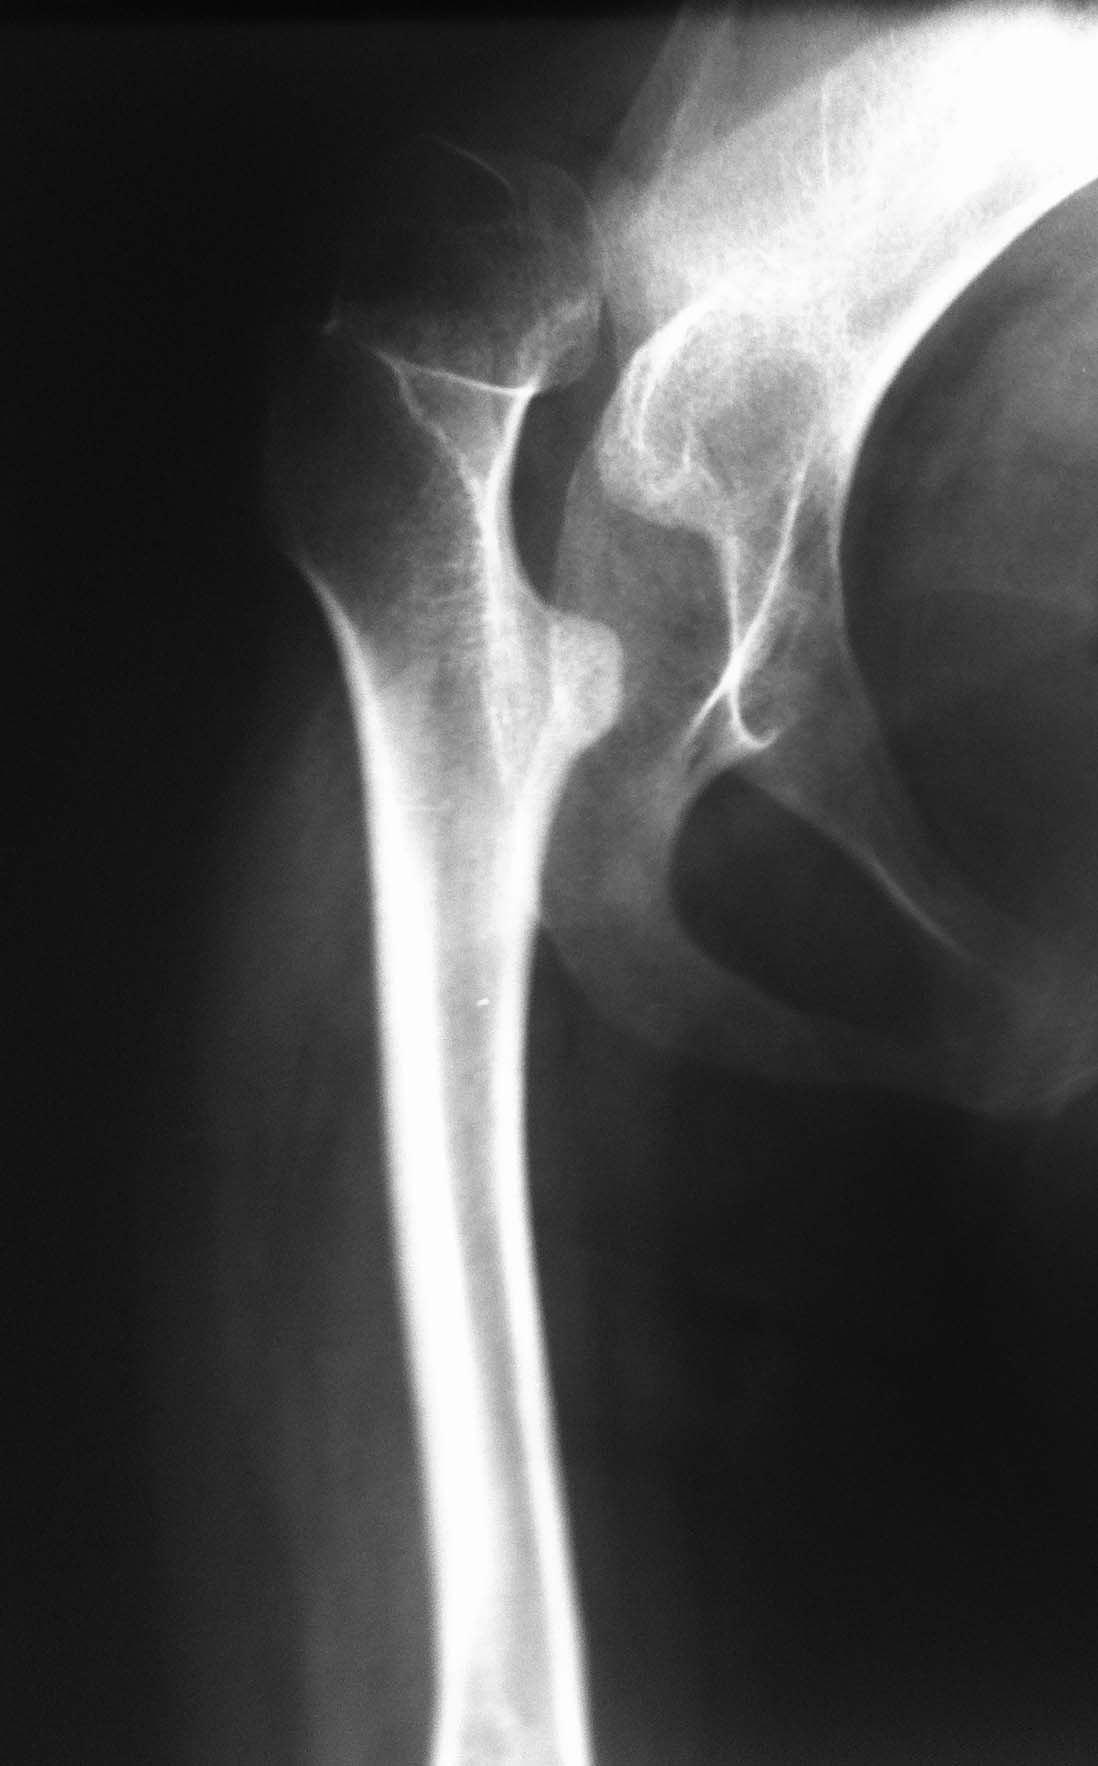

Пациентка 1992 г.р. Болеет ДЦП с рождения. до 2005 г. наблюдалась у неврологов , ходила с

поддержкой. В 2005 г. перелом средней трети бедра. Лечилась консервативно в больнице

Краснодара.

После лечения постепенно стала наростать укорочение конечности и искривление

позвоночника. На представленных Р-гр состояние на сегодняшний день. больная занимает

вынужденное полулежачее состояние. Вопрос где нибудь на просторах РФ могут помочь?????